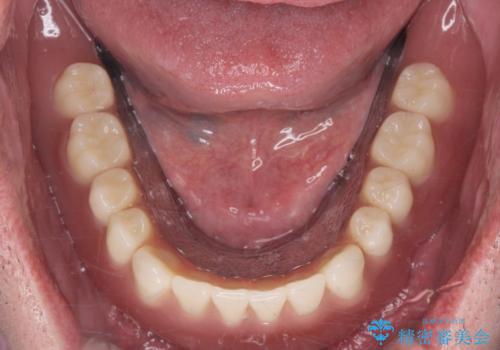

適合もよくしっかり噛めるようになりました。

見た目も改善されてとても満足して頂けました。